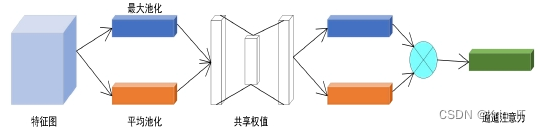

空间注意力机制(SAM)通过对输入特征图进行最大池化和平均池化操作,随后进行卷积处理,生成新的权值,从而获得更具代表性的特征。这一过程允许模型关注输入特征图中的重要区域。通道注意力机制(CAM)则通过分别对输入特征图进行最大池化和平均池化处理,然后利用共享权值生成新的特征,强化了模型对特征通道的关注能力。此外,卷积块注意力机制(CBAM)将空间注意力机制和通道注意力机制相结合,先对特征图进行空间注意力提取,再进行通道注意力处理,最终输出新的特征图。通过这些注意力机制的引入,网络能够更有效地提取和利用关键特征,显著提升目标检测的性能。